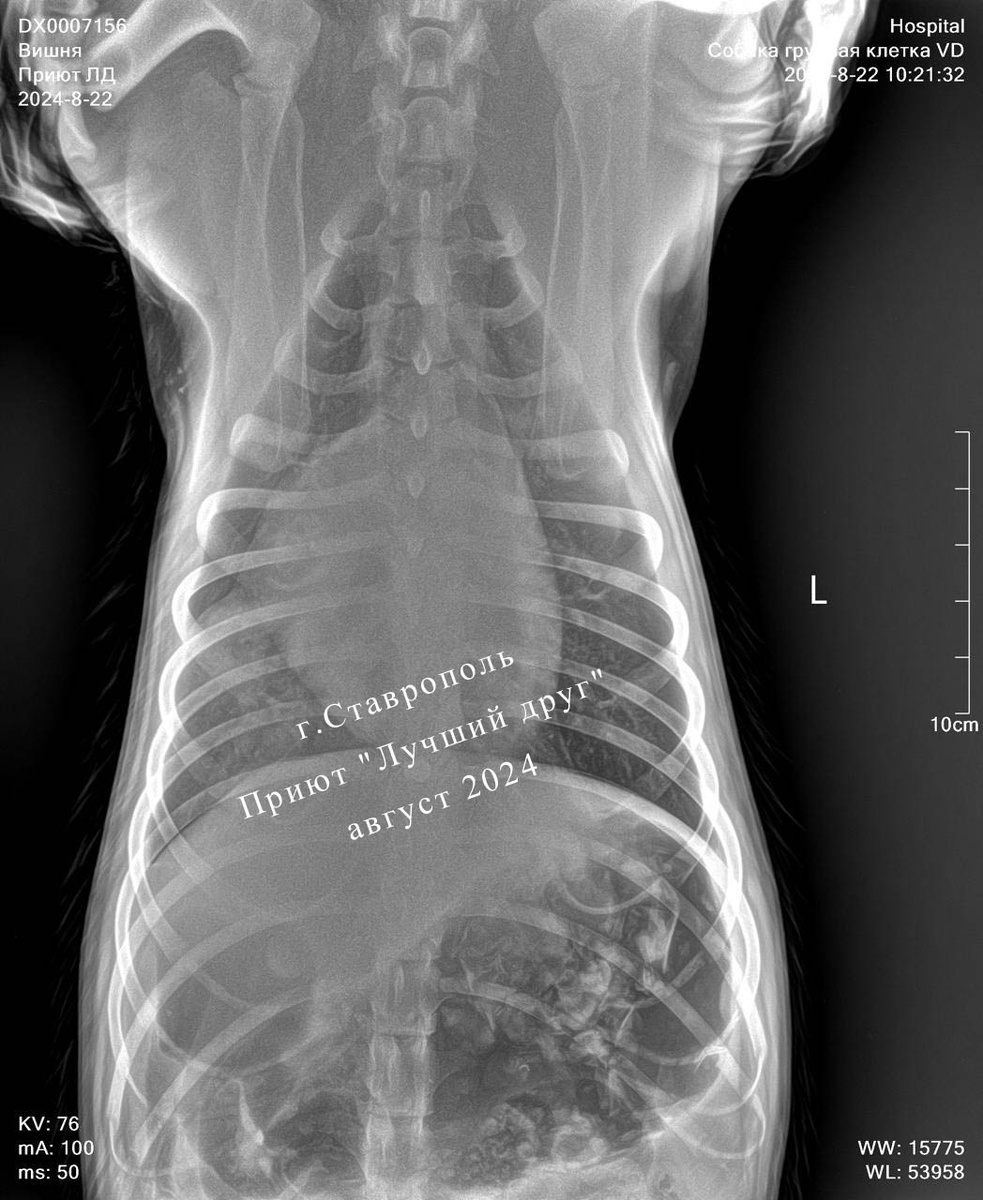

Думали, что собаку сбила машина и у нее сломаны лапы, но всё оказалось значительно хуже, в нее стреляли... У собаки слепое проникающее пулевое ранение грудного отдела позвоночника с компрессией спинного мозга и неврологическим дефицитом. Пулю удалось извлечь, собака перенесла операцию хорошо.